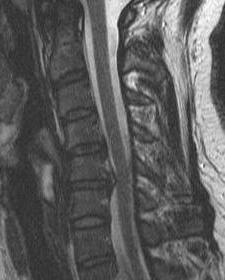

4. Evidence of cord edema / spinal cord damage

- often seen after acute injury in setting of stenosis

- best seen on STIR MRI

Spinal cord edema / injury